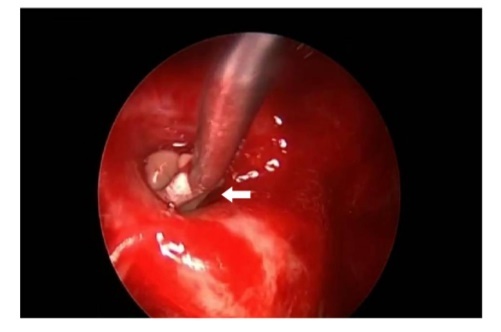

A 64-year-old lady presented to the outpatient department with complaints of headache and right eye blurring of vision for one month. Neurological examination revealed that bitemporal hemianopsia and impairment of visual acuity. Findings from fundus examination were within normal limits. Rest of the brain appeared unremarkable. Endocrine evaluation was normal. Results of renal function tests, liver function tests and haemogram test were within normal limits. A clinical diagnosis of non-secretory pituitary adenoma was made. Magnetic resonance imaging showed a well-circumscribed contrast-enhancing lesion in the sella (Figure 1, Figure 2). The patient underwent an endoscopic endonasal/transsfenoidal surgery in the supine position and total lesion resection was peformed. Intraoperatively, the lesion was found to be yellow colour, soft and avascular and it was removed totally until the sella turcica was visualized (Figure 3).In histopathologic examination septate hyphae were observed between inflammatory cells, Grocott staining is positive, but acid-fast stain for acid-fast bacilli (AFB) was negative. Histopathological findings suggest that infection of Actinomyces (Figure 4, Figure 5). We performed to patient consulted by patients to infectious diseases clinic. Patients underwent intravenous 6x2 gr ampicillin for four weeks.Then oral 4X500 mg amoxicillin treatment is planned a for at least 6 months. Patient did not have any deficits in the next six months.

Figure 3.White arrow shows in intraoperative image that the lesion was found as a yellow colour, soft and avascular shape